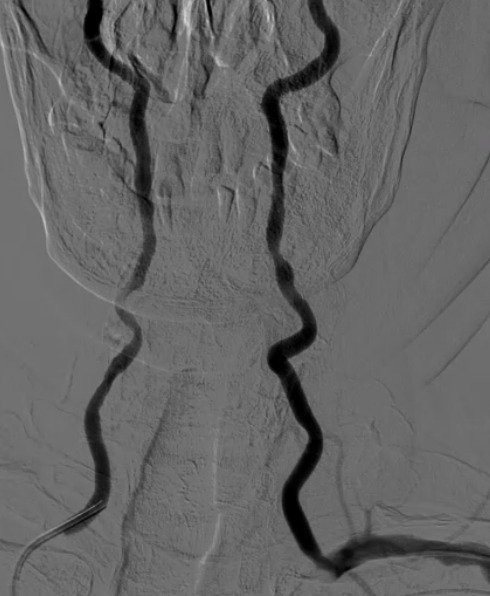

Blockages increasing risk of stroke

Advanced image-guided procedures performed for complex vascular and organ-based conditions.

MRI/CT interpretation and Thrombectomy and stenting/ plasty for acute and recurrent stroke. Cerebral DSA

Opening narrowed arteries to restore healthy blood flow.